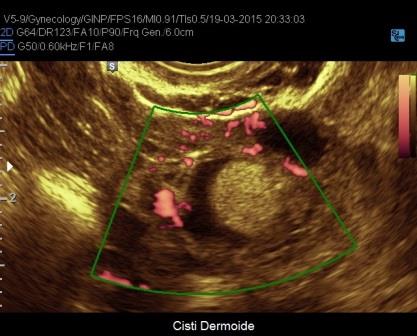

- il power doppler che consente di valutare la presenza di scarsa vascolarizzazione di parete e la assente vascolarizzazione delle aree di addensamento e delle irregolarità di parete;

- cisti dermoidi: sono in genere uniloculari, a contenuto disomogeneo, con aree ecogene dotate di cono d'ombra posteriore non vascolarizzate, non sono presenti i foci iperecogeni di parete a differenza degli endometriomi;